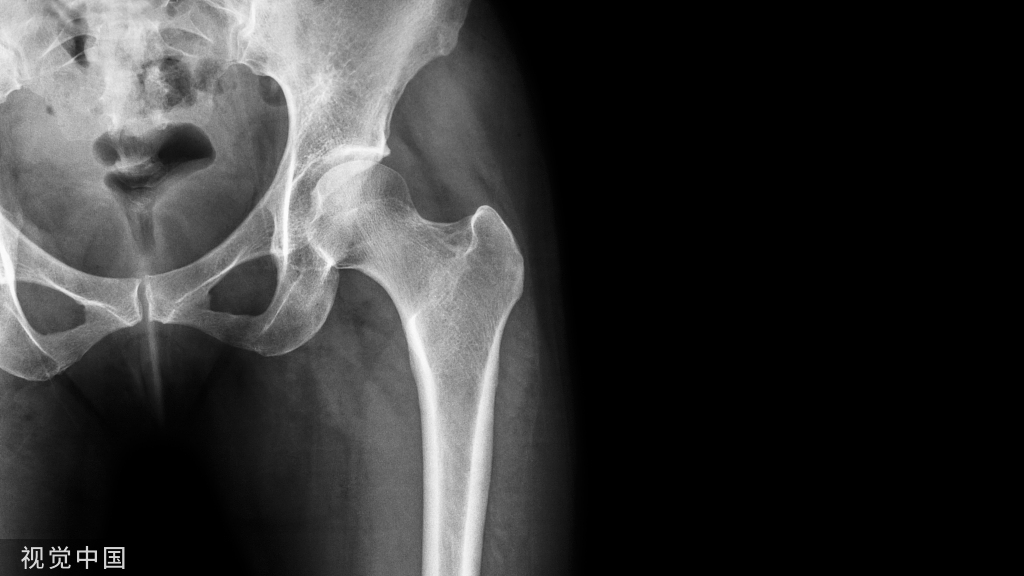

4.将Poller置于锐角处的干骺端或远端骨块;

图3 将Poller钉置于锐角处。